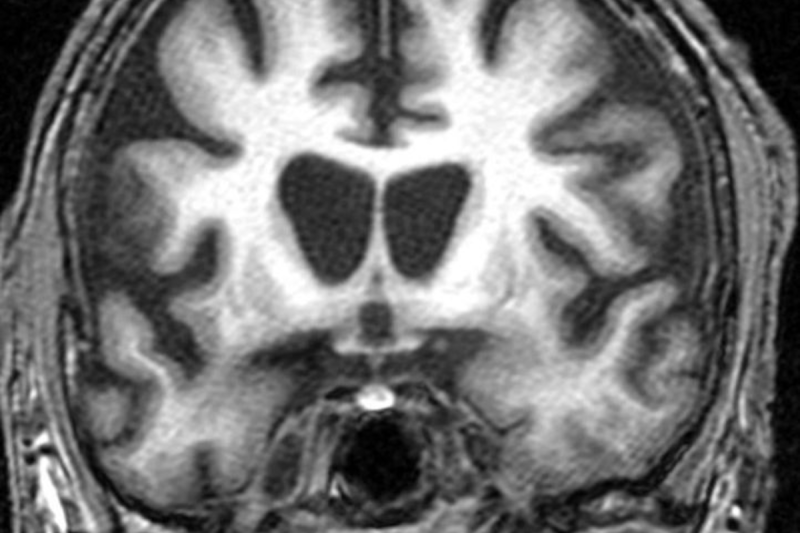

Gene Therapy Aims To Slow Huntington’s Disease To A Crawl

Despite the best efforts of modern medicine, Huntington’s disease is a condition that still comes with a tragic prognosis. Primarily an inher...